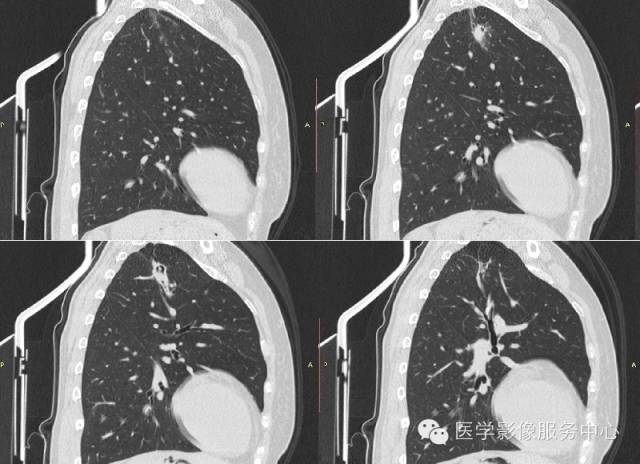

【病例】肺曲菌病1例CT影像表现

女,42岁,间断性咯血一年。

3、曲菌球:一般寄生在肺部慢性疾病所致的空洞或空腔内,常见的有结核空洞、支气管扩张、先天性肺囊肿等。空洞大小不等、洞壁薄厚不一,其内曲菌球一般呈圆形或卵圆形,密度均匀,边界光整,在洞内处于游离状态,可随体位改变而移动,曲菌球与洞壁之问形成一新月形的含气腔隙。曲菌球具有特征性的诊断价值。